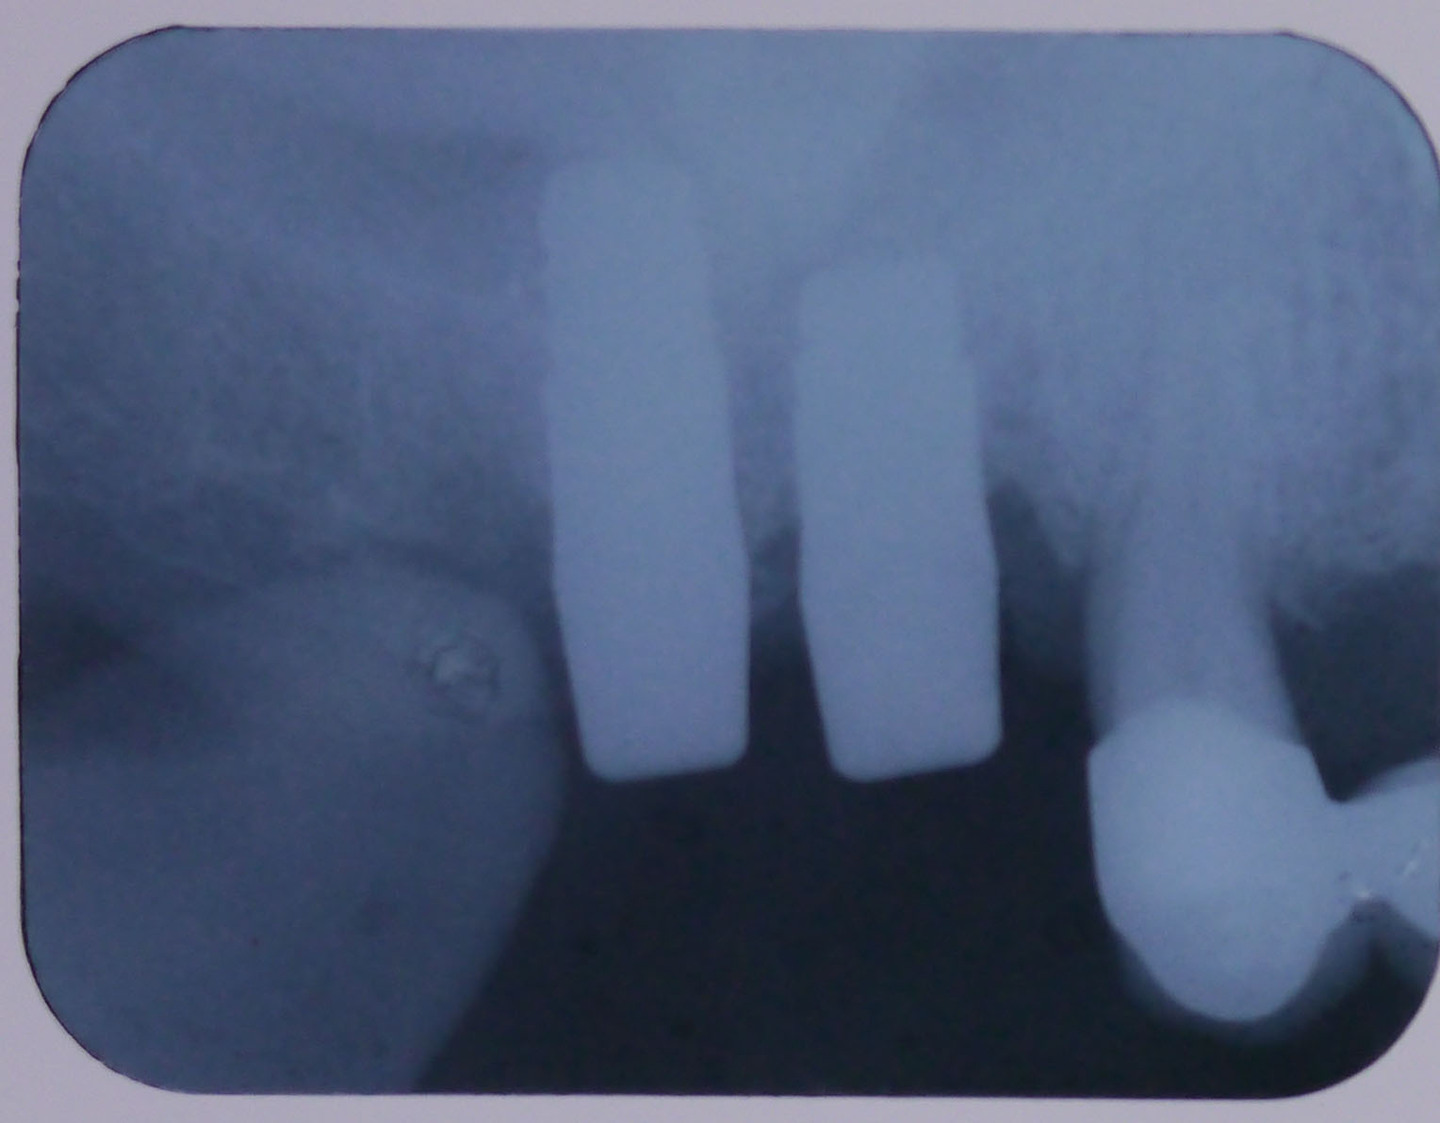

レントゲン画像1

平成24年9月11日の手術後のレントゲン画像

レントゲン画像2

平成25年1月16日、4ヶ月後のレントゲン画像

【レントゲン画像3】

平成29年3月3日定期検診時

十分に骨が維持されている